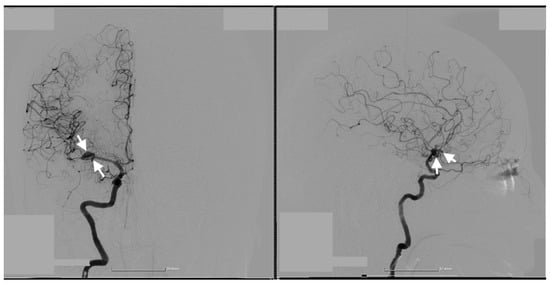

Cerebral angiography confirmed the presence of 2 ruptured saccular aneurysms at the bifurcation of the M1 segment of the right MCA (Figure 1, Figure 2 and Figure 3).

These rare vascular anomalies account for less than 1% of all intracranial aneurysms, making their diagnosis and management particularly challenging. Their anatomical proximity often results in misdiagnosis as a single, irregular, or lobulated aneurysm, increasing the risk of suboptimal treatment and delayed intervention [12,13,14]. In this case, advanced imaging techniques, particularly 3D digital subtraction angiography (3D-DSA), were pivotal in unraveling the precise configuration of the lesions. The high-resolution visualization provided by 3D-DSA allowed the identification of dual ruptures in the M1 segment of the MCA, facilitating a carefully tailored surgical strategy. Such precise imaging underscores the critical role of technology in transforming complex cases into manageable clinical scenarios [15,16].

Figure 2. Preoperative three-dimensional (3D) DSA rotational angiography. The 3D reconstruction of rotational DSA (left image) highlights the two kissing aneurysms (white arrows), one with 3 mm diameter and the other with a 7 mm diameter (right image).

Figure 3. Preoperative 3D DSA rotational angiography. In a high-resolution image, two kissing aneurysms are seen on the bifurcation of the M1 segment of the right MCA. The white arrows indicate the aneurysms' distinct locations, emphasizing their close proximity and shared arterial structures, which are characteristic of this rare vascular anomaly.